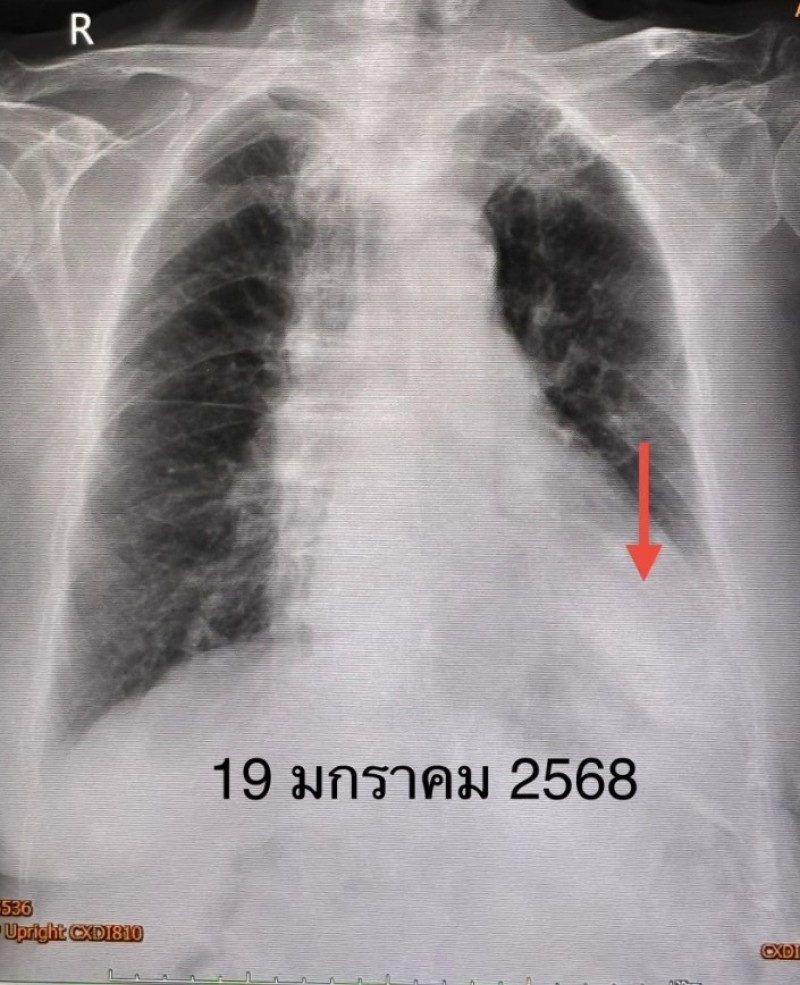

ตรวจร่างกาย ระดับออกซิเจนที่ปลายนิ้วต่ำ 87% ต้องให้ออกซิเจน 2 ลิตร/นาที ไม่มีไข้ ฟังปอดมีเสียงผิดปกติเล็กน้อยที่ปอดข้างซ้ายด้านล่าง เจาะเลือด เม็ดเลือดขาวในเลือดปกติ เอกซเรย์ปอดมีฝ้าขาวในปอดข้างซ้ายด้านล่าง ทำคอมพิวเตอร์ปอดยืนยันว่ามีฝ้าในปอดข้างซ้ายด้านล่าง และมีน้ำในช่องเยื่อหุ้มปอดเล็กน้อย ตรวจเลือดเม็ดเลือดขาวปกติ แยงจมูกส่งตรวจรหัสพันธุกรรมเชื้อ 22 สายพันธุ์ไม่พบเชื้อ ส่งเลือดตรวจ Legionella pneumophila Antibody IgM positive 1:200

วินิจฉัย : ติดเชื้อแบคทีเรียลีจิโอเนลลา นิวโมฟิลา Legionella pneumophila ทำให้ปอดอักเสบ ให้ยา azithromycin และ levofloxacin คนไข้ดีขึ้น ไม่ไอ ไม่เหนื่อย ระดับออกซิเจนปกติ ไม่ต้องใช้ออกซิเจน วันที่ 26 มกราคมเอกซเรย์ปอดกลับมาเป็นปกติ